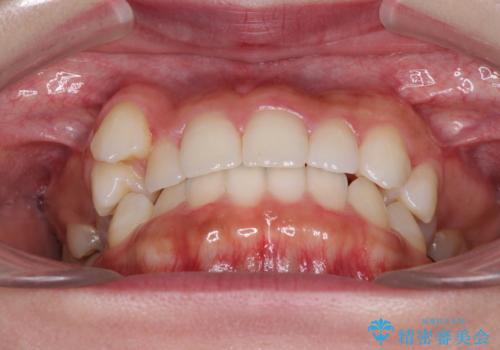

八重歯を改善 目立たないワイヤー装置での矯正治療

- 八重歯を気にして来院された患者様です。

本来であれば八重歯の隣後方の歯を抜歯するのですが、その後ろの歯が乳歯であり後続永久歯もなかったため、乳歯を抜去することとしました。

前から5番目の乳歯は、後続永久歯である小臼歯と比べて幅径が大きいため、移動に時間がかかりましたが、きれいに仕上げることができました。